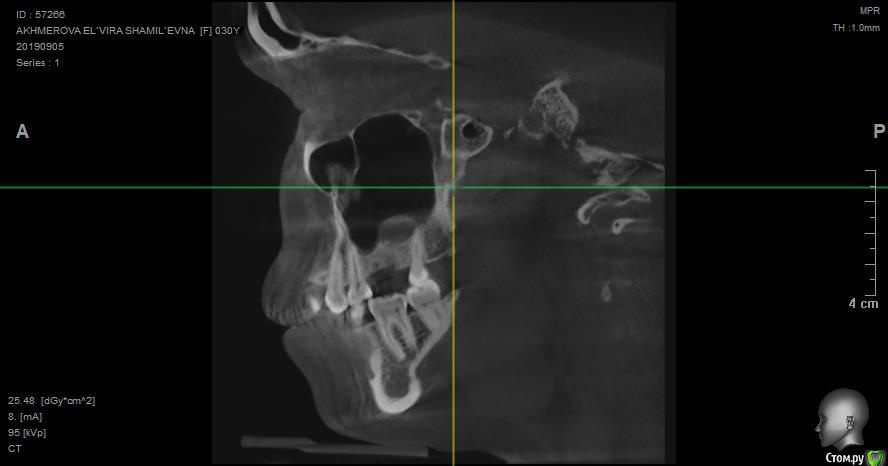

jelly Опубликовано 8 октября, 2019 Поделиться Опубликовано 8 октября, 2019 Добрый день! Посмотрите пожалуйста снимок, верхняя шестерка была удалена вместе с кистой еще в июне, до сих пор с этой стороны тянущая боль, отдающая в висок, шею и лицо. Один из лоров мне сказал, что там в одном месте есть изменения в кости. Подскажите пожалуйста, что делать дальше? Ссылка на снимки кт: https://disk.yandex.ru/client/disk/%D0%9A%D0%A2 Ссылка на комментарий

jelly Опубликовано 8 октября, 2019 Автор Поделиться Опубликовано 8 октября, 2019 КТ после удаления через 2,5 месяца сделано Ссылка на комментарий

jelly Опубликовано 9 октября, 2019 Автор Поделиться Опубликовано 9 октября, 2019 И вот еще. Ссылка на комментарий

Irouil Опубликовано 9 октября, 2019 Поделиться Опубликовано 9 октября, 2019 Судя по всему растёт резидуальная киста. Надо удалять Ссылка на комментарий